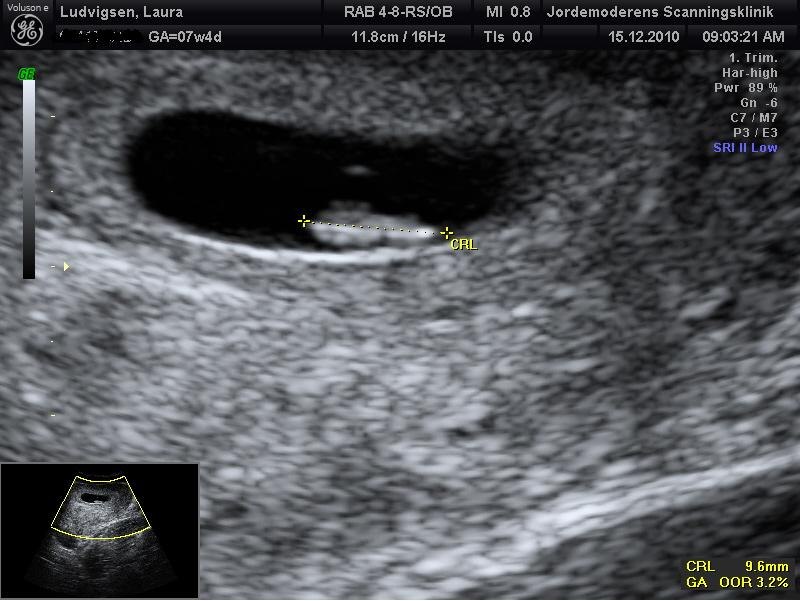

nu glæder jeg mig da helt vildt til i morgen, der er jeg 7+5 og skal scannes det blir lidt sjovt, og dine billeder er meget fine og grunden til at de er forskellige er bla. vinkler og det pres der bliver på/i maven under en scanning, og ja man kan godt se det er en begyndende baby du har der så tillykke